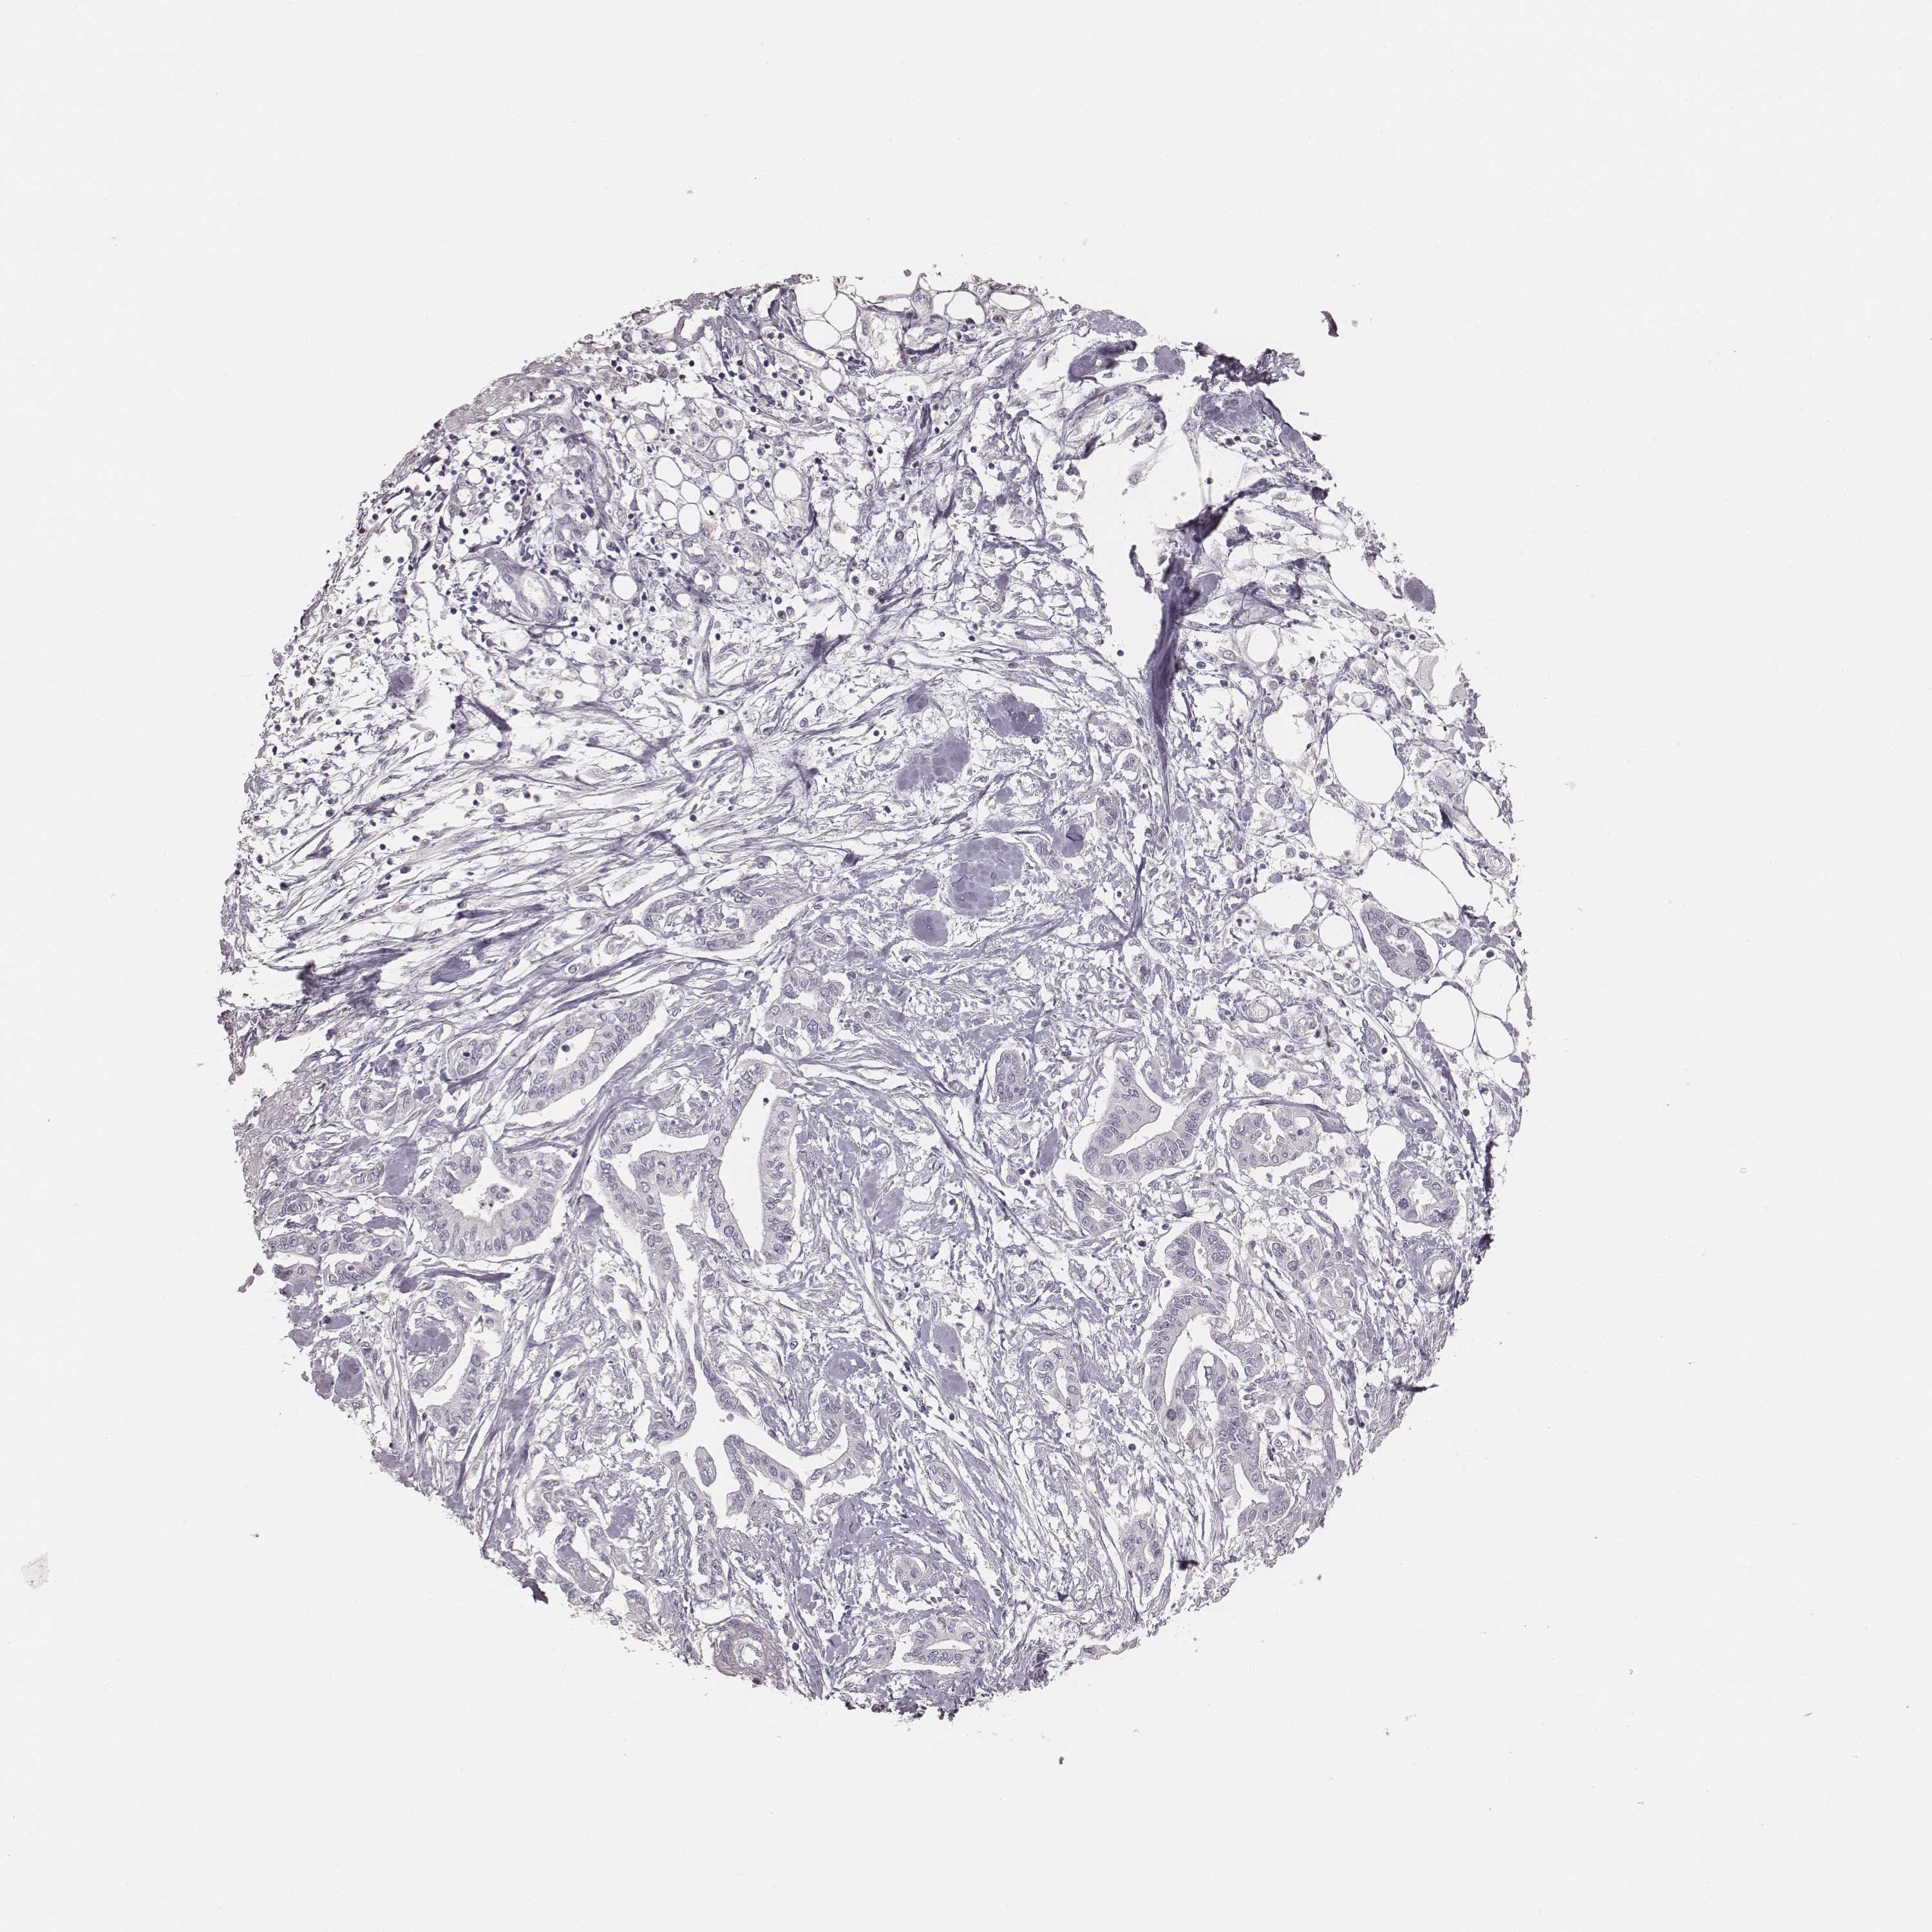

PANCREATIC CANCER - Protein expressioni

A mouse-over function shows sample information and annotation data. Click on an image to view it in a full screen mode. Samples can be filtered based on level of antibody staining by selecting one or several of the following categories: high, medium, low and not detected. The assay and annotation is described here.

Note that samples used for immunohistochemistry by the Human Protein Atlas do not correspond to samples in the TCGA dataset.

Antibody stainingi

Antibody staining in the annotated cell types in the current human tissue is reported as not detected, low, medium, or high, based on conventional immunohistochemistry profiling in selected tissues. This score is based on the combination of the staining intensity and fraction of stained cells.

Each image is clickable and will lead to virtual microscopy that enables deeper exploration of all samples and also displays staining intensity scores, fraction scores and subcellular localization as well as patient and tissue information for each sample.

Antibody HPA049550

Antibody HPA055194

Staining

High

Medium

Low

Not detected

Intensity

Strong

Moderate

Weak

Negative

Quantity

>75%

75%-25%

<25%

None

Location

Nuclear

Cytoplasmic/membranous

Cytoplasmic/membranous,nuclear

Adenocarcinoma, NOS